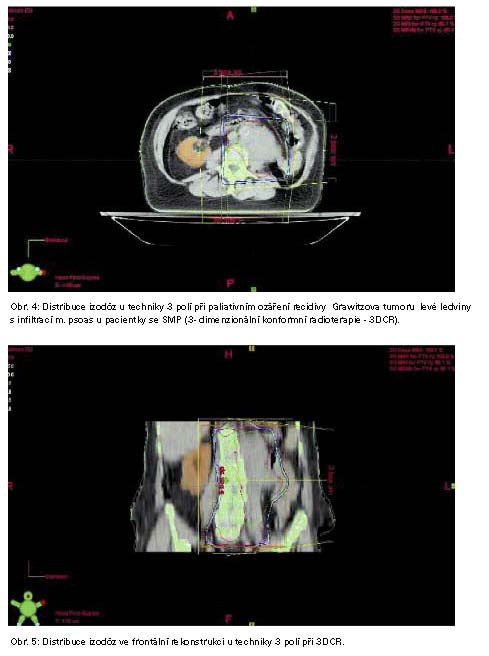

Léčba SMP zářením byla u 4 pacientů (obr. 4., 5., 6.) zářením, imunoterapii 1x a chemoterapií 1x.